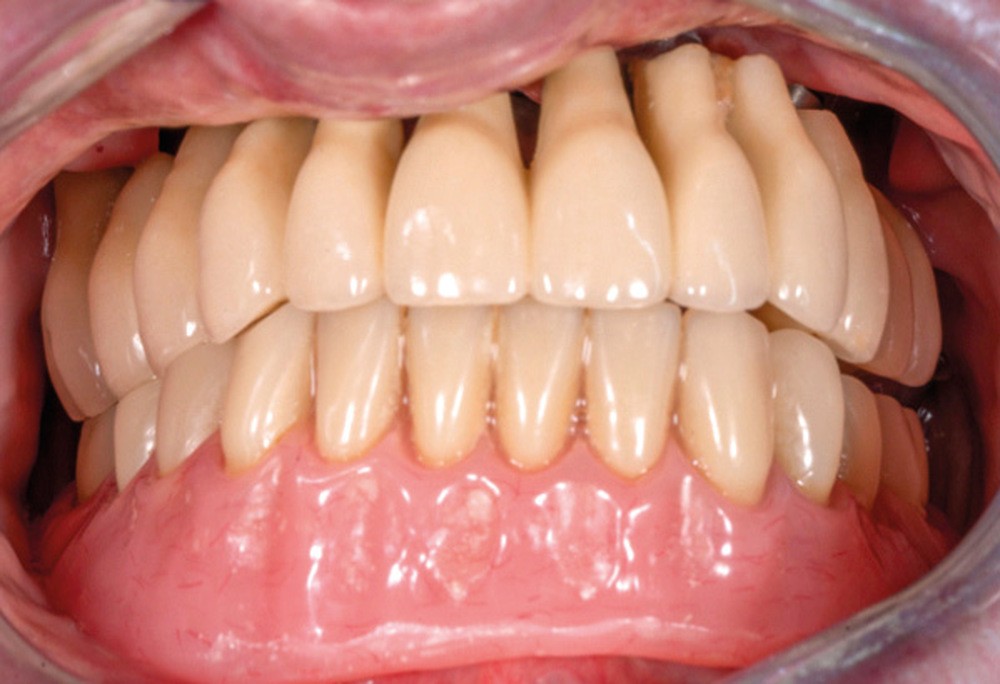

La détermination d’un positionnement correct du maxillaire dans le massif cranio-facial est essentielle lors d’une réhabilitation prothétique étendue. Plans et lignes de références permettent de transférer la position du maxillaire sur articulateur et d’évaluer l’agencement dentaire avec l’harmonie globale du visage [1]. La conception et la réalisation d’une prothèse complète, amovible ou transvissée, sont des exercices difficiles pour le praticien, comme pour le prothésiste de laboratoire, qui doivent imaginer et recréer de manière optimale les fonctions et l’esthétique perdues [2].

En prothèse amovible complète, le plan d’occlusion correspond au plan selon lequel seront montées les dents prothétiques. En règle générale, il passe par le bord libre des deux incisives centrales et le bord distal des deuxièmes molaires inférieures [2]. Outre des répercussions d’ordre esthétique, un plan d’occlusion erroné peut perturber la cinématique mandibulaire, générer un inconfort, une impotence, voire un handicap fonctionnel. Des conséquences pathologiques à long terme telles que des myoarthropathies de l’appareil manducateur peuvent aussi se manifester [2].

Dans le cas clinique présenté dans cet article, le patient édenté total bimaxillaire se plaint d’une gêne importante et d’une insatisfaction de son sourire en lien avec un plan d’occlusion prothétique inadapté (fig. 1 et 2).

Chez l’édenté total, la bonne orientation du plan d’occlusion prothétique permet de répondre à des impératifs fonctionnels et esthétiques :

L’orientation du plan d’occlusion est primordiale, car elle influe sur la puissance masticatoire du patient [3]. De plus, celui-ci assure également la stabilité des prothèses lors de la mastication. Un plan d’occlusion erroné peut créer une certaine instabilité et une inefficacité…